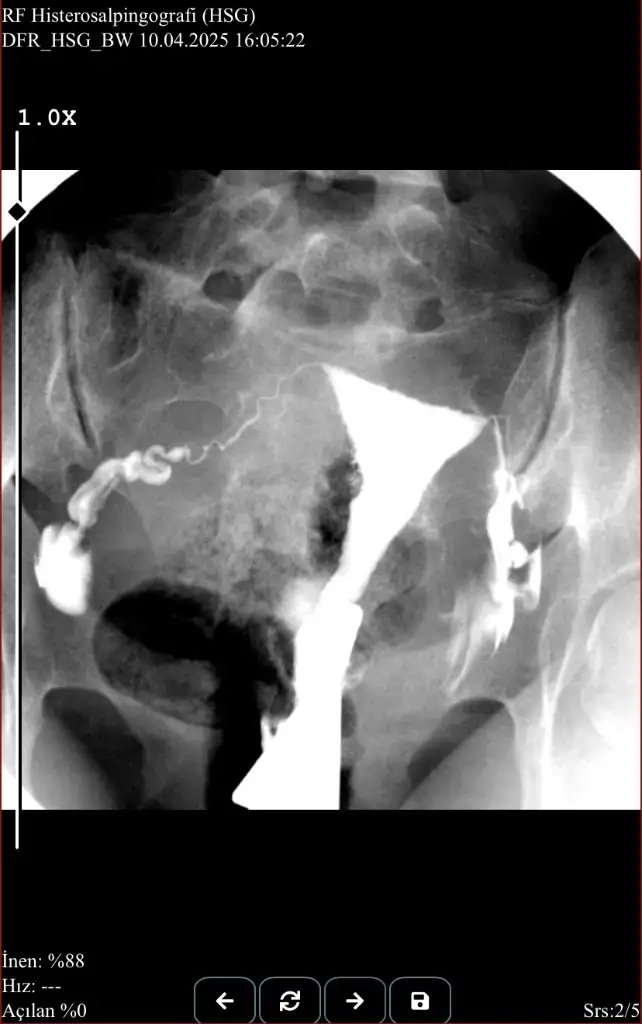

Merhaba

10 nisanda anestezisiz rahim filmi çektirdim.

Yorumlayabilecek olan var mı acaba?

• IMG_7326.webp

23,3 KB · Görüntüleme: 159